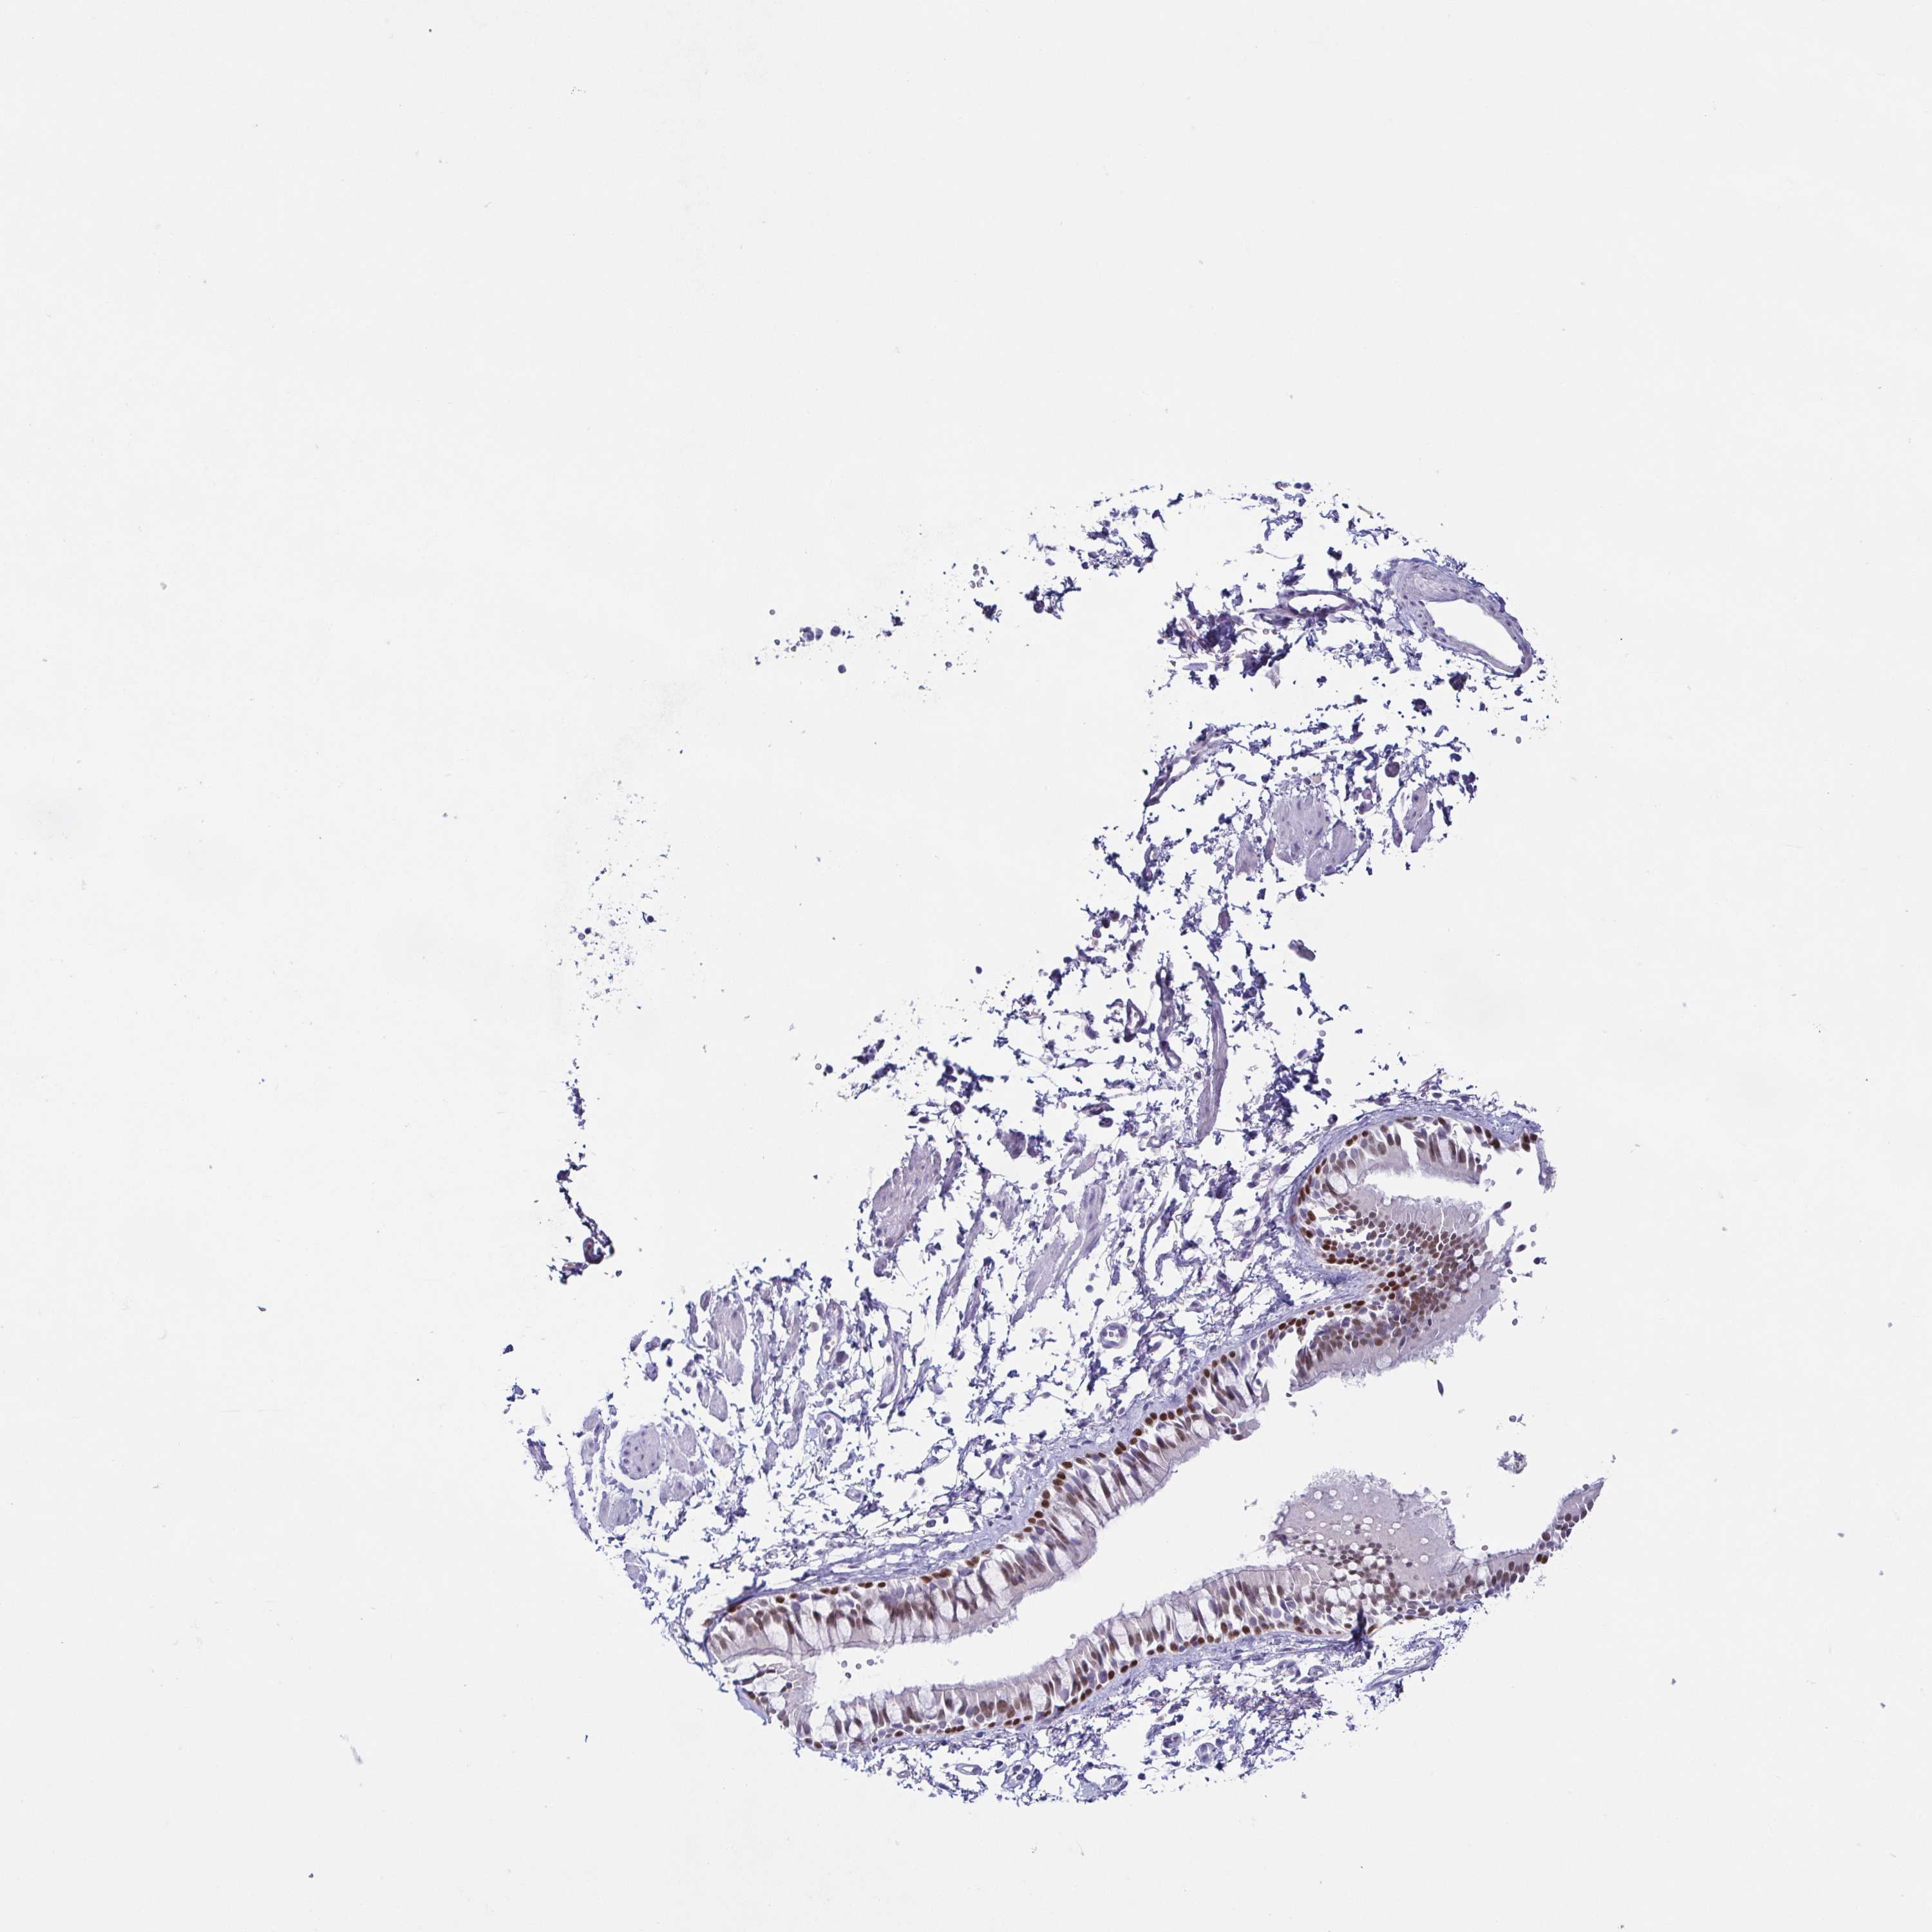

TISSUE PRIMARY DATA BRONCHUS Show tissue menu

BRONCHUS - Antibody stainingi

Antibody staining in the annotated cell types in the current human tissue is reported as not detected, low, medium, or high, based on conventional immunohistochemistry profiling in selected tissues. This score is based on the combination of the staining intensity and fraction of stained cells.

Each image is clickable and will lead to virtual microscopy that enables deeper exploration of all samples and also displays staining intensity scores, fraction scores and subcellular localization as well as patient and tissue information for each sample.

Antibody CAB002514Antibody CAB003022

Basal cells High-

Ciliated cells (cell body) Not detected-

Ciliated cells (cilia axoneme) Not detected-

Ciliated cells (ciliary rootlets) Not detected-

Ciliated cells (tip of cilia) Not detected-

Goblet cells Not detected-

Respiratory epithelial cells -Medium